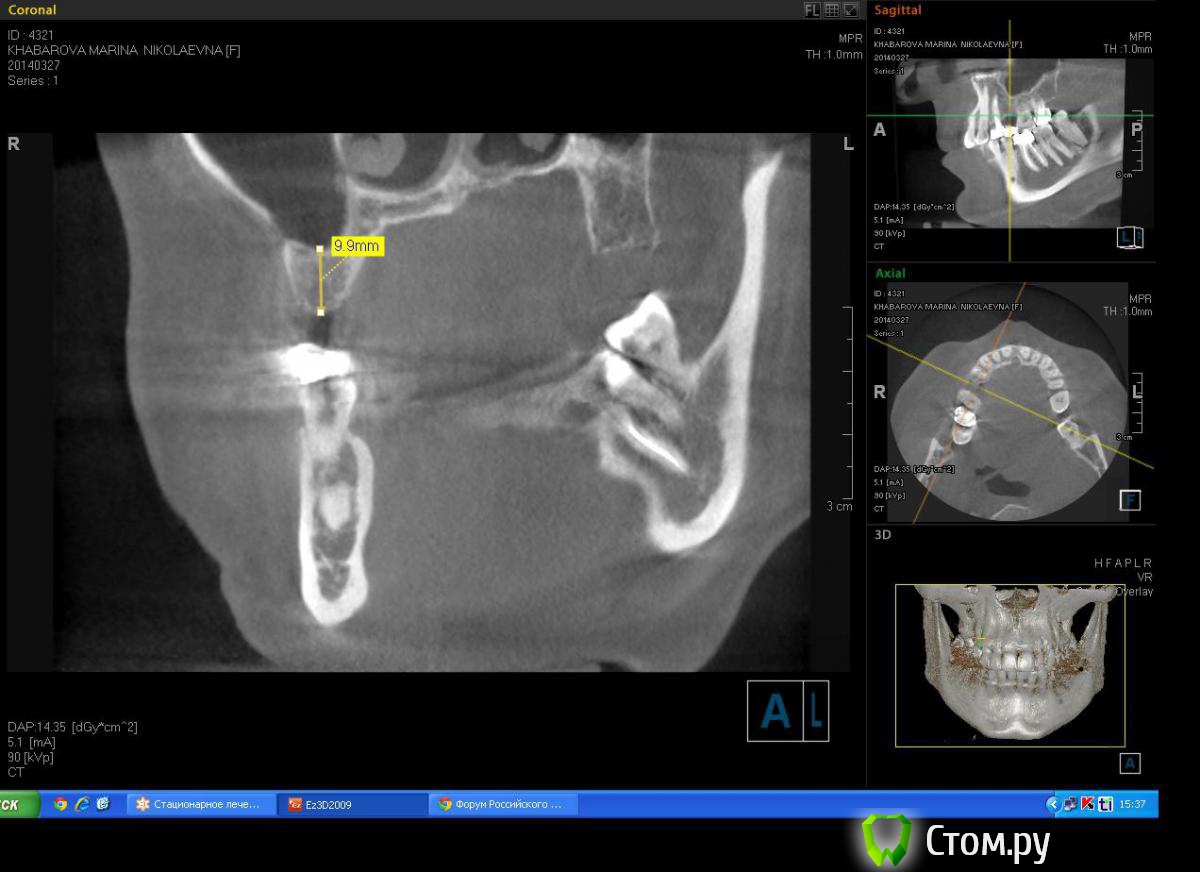

Milanomoda Опубликовано 22 апреля, 2014 Автор Поделиться Опубликовано 22 апреля, 2014 Имплантацию в районе 14 зуба планирую ставить в область язычного корня, только вот вопросик такой, при одномоментном протоколе на сколько примерно заглублять нужно будет имплант? Ссылка на комментарий

DShu Опубликовано 22 апреля, 2014 Поделиться Опубликовано 22 апреля, 2014 4,2 думаю им там тесновато будет. 4,5 тем более.На 14 я бы поставил 3,75*16 (или на 13) на 15 - 3,75*10 бикортикально. Сразу формики, вокруг - графт или без него, кто как любит) 3 Ссылка на комментарий

Milanomoda Опубликовано 22 апреля, 2014 Автор Поделиться Опубликовано 22 апреля, 2014 4,2 думаю им там тесновато будет. 4,5 тем более.На 14 я бы поставил 3,75*16 (или на 13) на 15 - 3,75*10 бикортикально. Сразу формики, вокруг - графт или без него, кто как любит)Если в области 15 делать бикартикальную фиксацию то без синуса(закрытого) не обойтись, а если делать без синуса - то при нагрузке мне кажется слизистая гайморовой среагирует, не даром же от анатомических образований рекомендуют около 2 мм отступать... Ссылка на комментарий

Milanomoda Опубликовано 28 апреля, 2014 Автор Поделиться Опубликовано 28 апреля, 2014 А можно увидеть замер расстояния между 13 и 16 и промеры толщины гребня? ИМХО, 4,2 в области премоляров - не самый лучший вариант и я не уверен, что "все будет ОК" Спасибо за беспокойство, в прошлую пятницу принимал даную пациентку. Вообщем в итоге при удалении зуба 14 произошел отлом щечной стенки, причем такой приличный, она была толщиной мне кажется тоньше чем листок бумажки. Вообщем в область 15 поставил 4.2\8, а лунку зуба 14 пришлось наполнять графтом(BondBone) и планировать отсрочено. Ссылка на комментарий